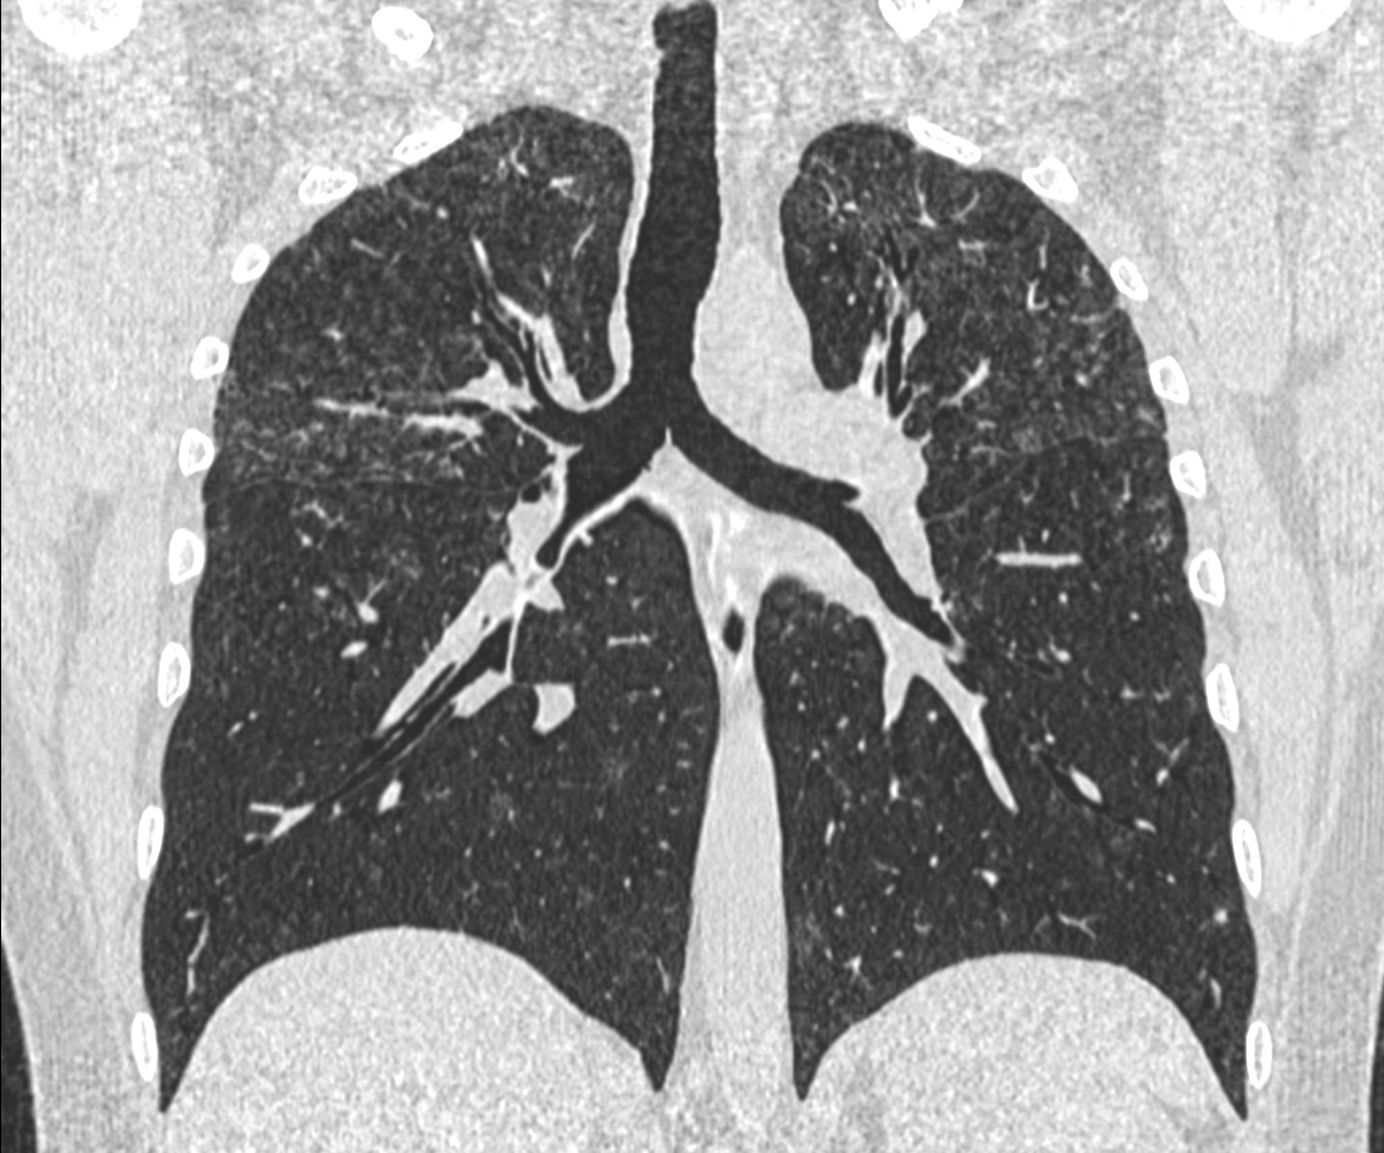

The PDIF sign is basically the presence of a fibrosing ILD typically compacted within the last 2 cm of the peridiaphragmatic lung and may suggest not just CTD-ILD but specifically myositis ILD